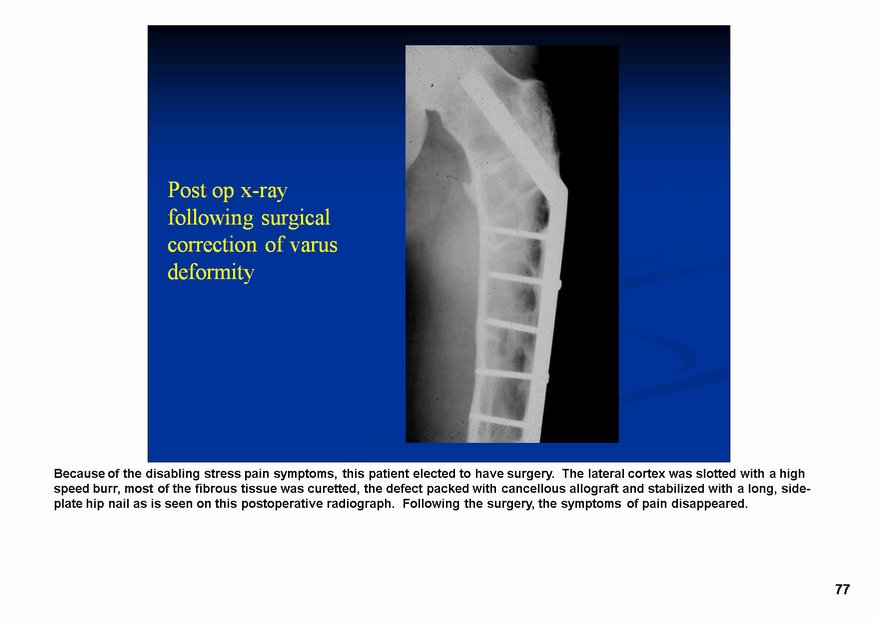

Фиброзная дисплазия — заболевание, характеризующееся нарушением развития (дисплазия) скелета, при котором нормальная кость замещается фиброзной тканью с элементами диспластически изменённой кости. Выделяют монооссальную (около 85% случаев), мономелическую (поражено несколько соседних костей одной конечности, плечевого или тазового пояса) и полиоссальную (около 5% случаев) формы. Фиброзная дисплазия как аномалия развития иногда сочетается с внескелетными расстройствами: 1) полиоссальная форма поражения сочетается с преждевременным половым созреванием и пигментными пятнами на коже в виде кофейных пятен (Albright’s syndrome); 2) сочетание фиброзной дисплазии с миксомами мягких тканей (Mazabraud’s syndrome). Встречается в любом возрасте, наиболее часто в первые 3 десятилетия жизни (70% больных). Монооссальная форма несколько чаще встречается у лиц мужского пола, при полиоссальной форме соотношение лиц мужского и женского пола 2 : 1. Поражается любая кость, наиболее частая локализация: проксимальная часть бедренной кости, большеберцовая и плечевая кости, рёбра, кости черепа, шейного отдела позвоночника. Поражение костей позвоночника только в 2,5% случаев.